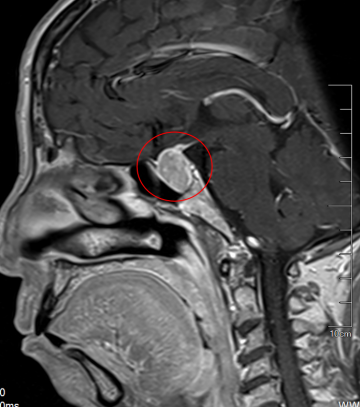

來到泰康同濟(jì)(武漢)醫(yī)院后,眼科陳中山主任憑借豐富經(jīng)驗(yàn),敏銳地察覺到患者長期不明原因的視力下降可能與顱內(nèi)病變有關(guān),轉(zhuǎn)診至神經(jīng)外科后,陳勁草教授懷疑是“垂體瘤”,建議完善頭部CT檢查。隨后的腦部MRI檢查證實(shí)了他的判斷:兩位患者鞍區(qū)均存在垂體占位性病變,腫瘤壓迫視交叉神經(jīng)導(dǎo)致了視野缺損和視力下降。

隨后,由陳勁草教授主刀,帶領(lǐng)神經(jīng)外科團(tuán)隊(duì),成功為兩位患者實(shí)施了“顯微鏡下經(jīng)鼻蝶入路手術(shù)”,精準(zhǔn)地切除了腫瘤,術(shù)后病理診斷均為垂體腺瘤。手術(shù)效果顯著:術(shù)后,陳婆婆的左眼視力恢復(fù)至0.5,右眼視力提升至0.8;張先生術(shù)后僅3天,視力便恢復(fù)至1.0。